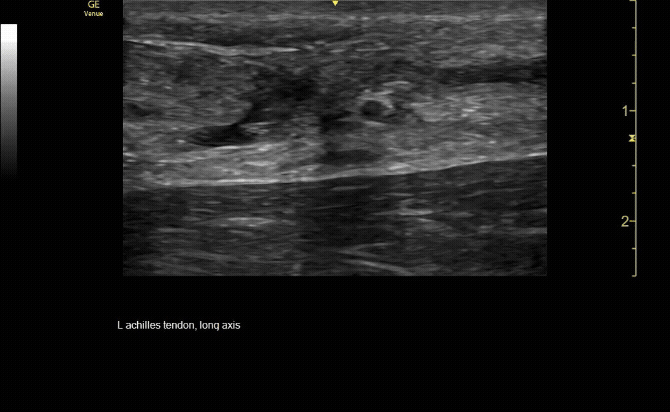

Sagittal view of achilles tendon rupture.

c/o Jasmine Hill, MD